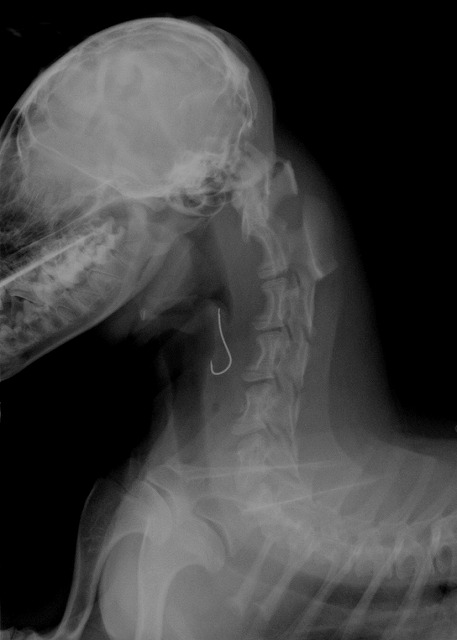

レントゲン検査をしてみると食道の中に釣針が引っかかっているようです!

Img6492-1.jpg